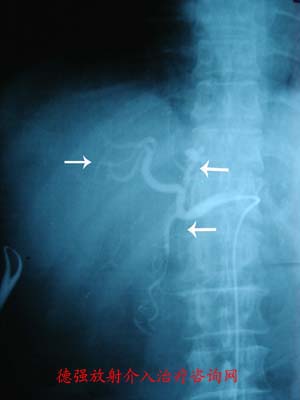

目前对肝血管瘤的治疗方法存在较大争议,主要有血管瘤切除术、血管瘤缝扎术、肝动脉结扎术、微波固化术、射频治疗、肝动脉栓塞术等。对于弥漫性的肝血管瘤,或者无法切除的巨大血管瘤,如肝功能失代偿或合并Kasabach-Merritt综合征,也可行肝移植治疗。对于需要治疗的肝血管瘤,应综合多种因素考虑,以病人获益、安全、有效为原则,依据医生的技术水平和经验,多种因素间权衡,选择不同的治疗方式。